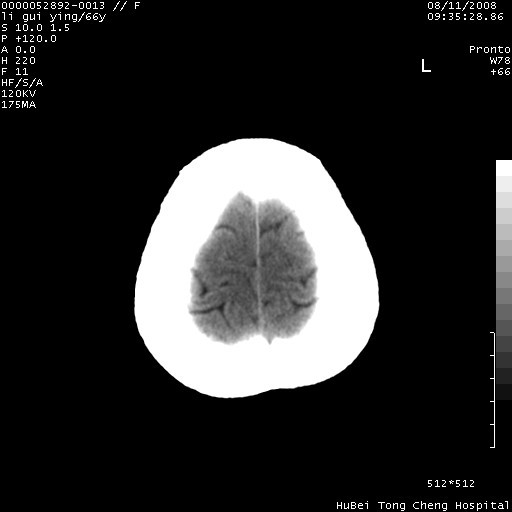

以下是引用yangyudong333在2008-8-12 12:22:00的发言:[br]1.病灶呈圆形[br]2.周围无水肿带[br]3.密度不均匀,内有点状钙化[br]4.无占位效应[br] 考虑良性占位性病变,血管瘤可能性大